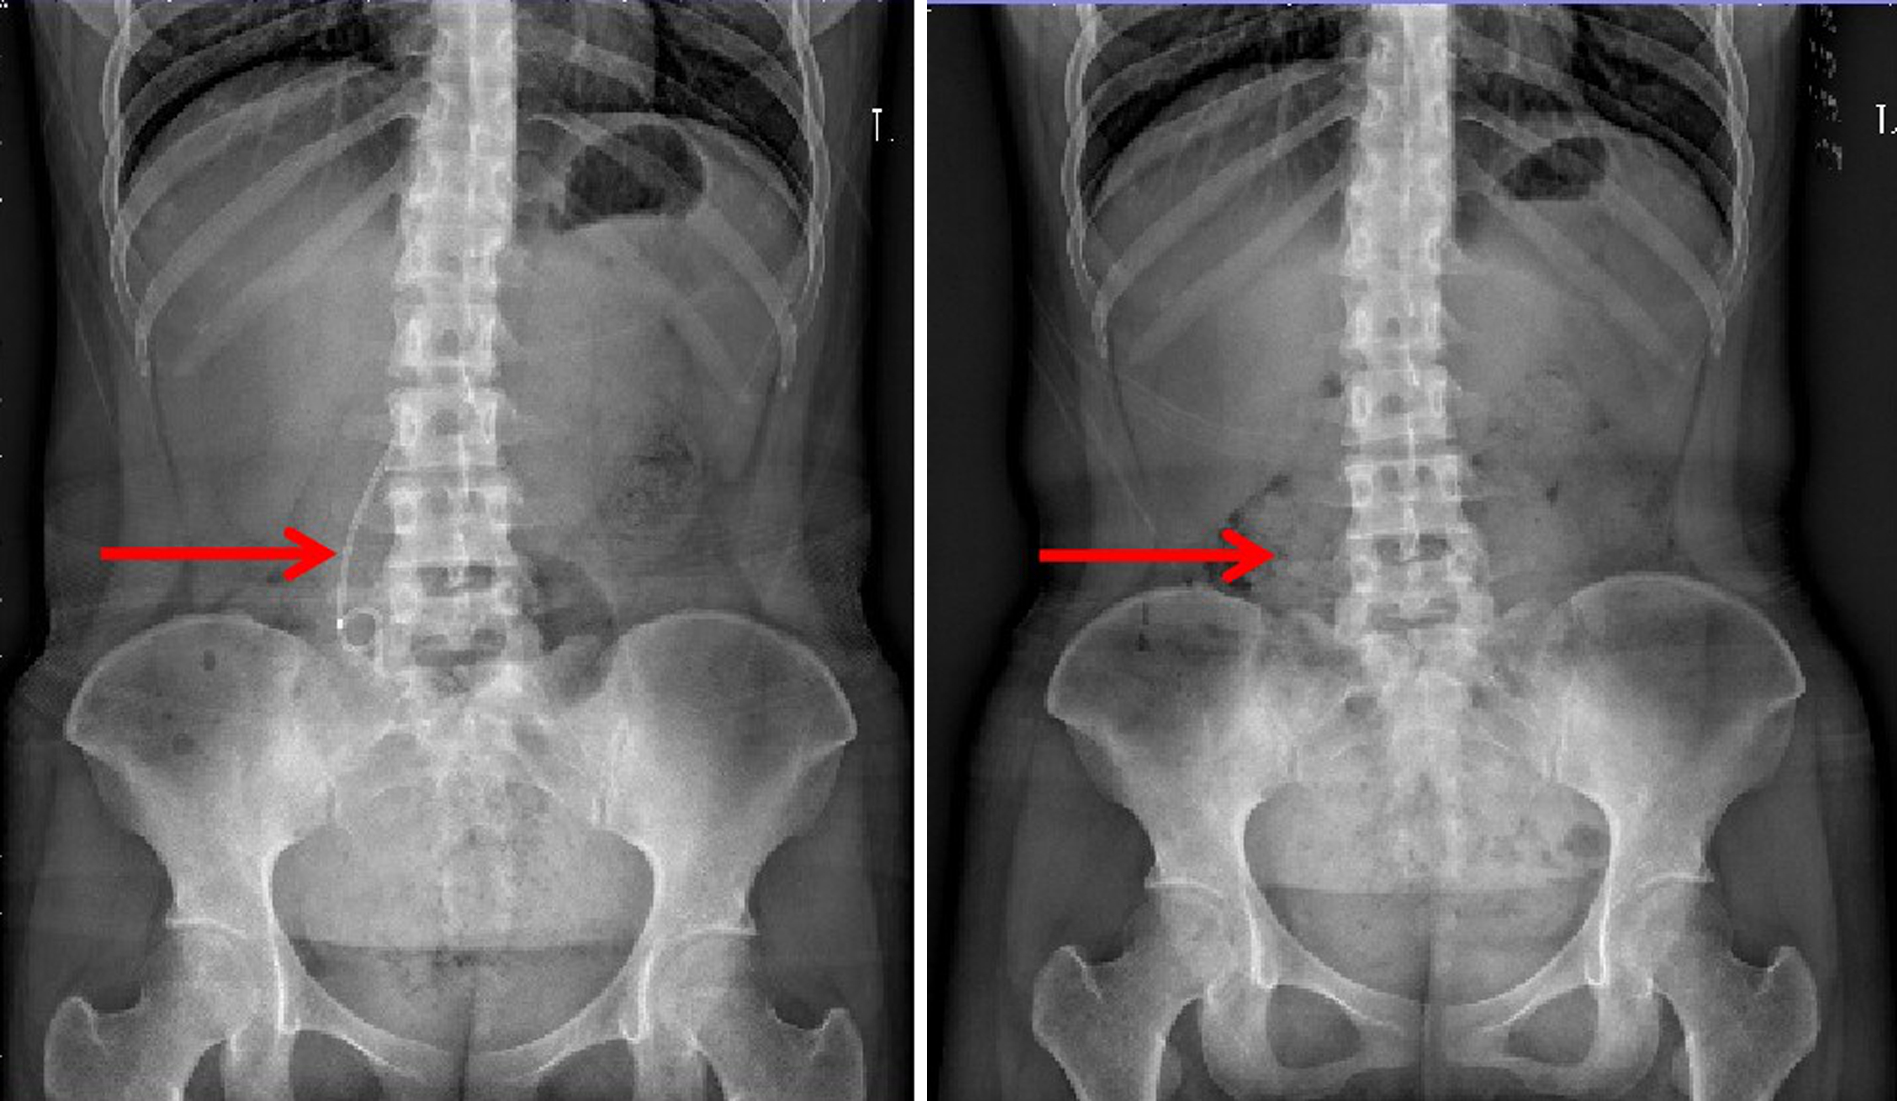

Sepsis with spontaneous splenic rupture and hemorrhage: A case report

Zhou LIU, Wenfang XIA, Liying ZHAN, Xiaoyu FANG, Liang ZHANG, Na ZHAN, Rong YU, Li HANG, Lei ZHU

2023, 39(8): 1926-1931. DOI: 10.3969/j.issn.1001-5256.2023.08.024

Abstract(1289) HTML (293) PDF (4249KB)(98)

Abstract:

Severe infections due to sepsis often result in multi-organ insufficiency, such as cardiac insufficiency, renal insufficiency, hypohepatia, septic encephalopathy, coagulation dysfunction etc. Severe infections not only cause inflammatory storm, but also induce spleen abscess, and even combined with spontaneous splenic rupture hemorrhage. Spontaneous splenic rupture has an insidious onset, usually without a history of trauma, and is easily missed diagnosis. In this case, the patient with sepsis had sudden onset of abdominal pain and progressive decrease in hematocrit, thus the abdominal CT was immediately performed. The perisplenic mixed high-density shadow indicated splenic hemorrhage. After consultation with the department of hepatobiliary surgery, emergency dissection was performed. Splenic hematoma and laceration were found during the operation, thus total splenectomy was conducted. Pathological indicated chronic inflammatory cell infiltration of spleen, spleen abscess with bleeding. After operation, the patient's hematocrit was stable, abdominal pain improved significantly, and he was discharged from hospital after systematic therapy.